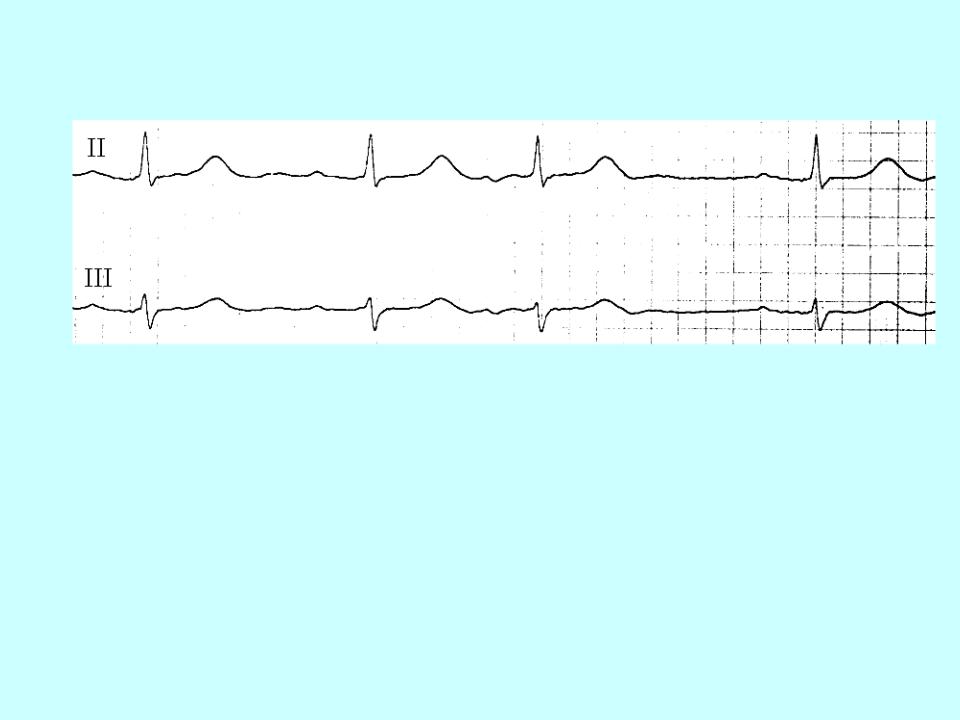

Ventricular extrasystole:

This is a premature excitatory impulse occurs in various parts of the conducting system ventricles.

The main ECG signs: Premature contraction

1.Absence of the P wave in the extrasystolic complex.

2.Significant expansion (more about, 1 s) and deformation ventricular complex (splitting, bifurcation teeth, serration, large amplitude compared to normal complexes).

3.Discordant displacement of the R (S) -T segment and the T wave (asymmetrical two-phase or negative) on in relation to the main tooth of the QRS complex.

4.Usually full compensatory pausе.